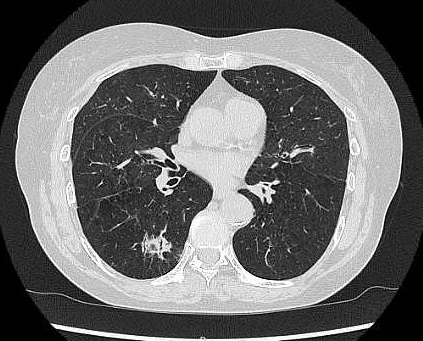

CT検査

CT検査はがん診療において様々な用途で行われます。

肺がんはCT検査で存在診断が可能です。肝がんなどは造影剤を使用することで病気内の血行動態を知ることができ質的診断が可能です。

また、病気周囲の血管の走行を知ることもできるため、手術の安全性を確認することができます。CT検査は短時間で広範囲に検査することができます。

胸部単純CT検査画像(右肺がん)